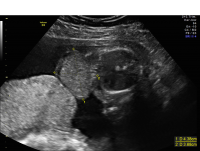

Omphalocele

Omphalocele is a type of “ventral wall defect” which is diagnosed when some of the organs of the abdomen protrude through an opening in the abdominal muscles near the umbilical cord insertion into the body. These organs are covered by a clear sac or membrane. Small omphaloceles are seen in one out of every 5,000 newborns, whereas giant omphaloceles are less common, and occur in one of every 10,000 newborns.

Omphalocele axial view